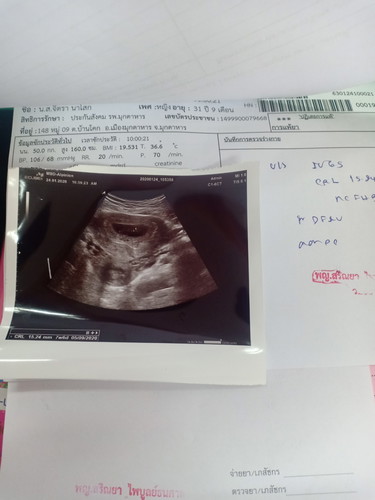

น้องไม่อยู่แล้ว ตื่นมาตอนเช้าเข้าห้องน้ำ มีเลือดไหลนิดหน่อย มาหาหมอ หมอบอกว่าน้องไม่แข็งแรง หัวใจหยุดเต้นแล้วว ไม่มีอาการใดๆให้อิแม่รับมือเลย อิแม่เสียใจมาก ร้องไห้หนักมาก??